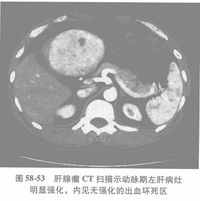

CT检查:肝内肿瘤部位可见密度减低区,近似囊性肿物。